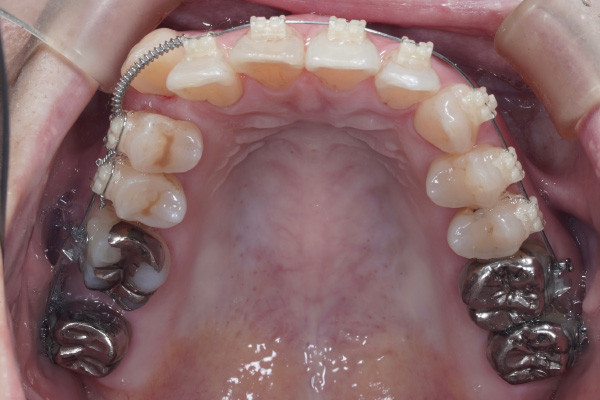

ワイヤー矯正でどこが変わる?

矯正治療では、歯を動かす「力」を計画的にかけることで、

⚫︎八重歯の位置

⚫︎前歯の咬み合わせ

⚫︎歯列全体のバランスが少しずつ改善していきます。

この症例の場合も、4ヶ月→8ヶ月で目に見える変化がありました。